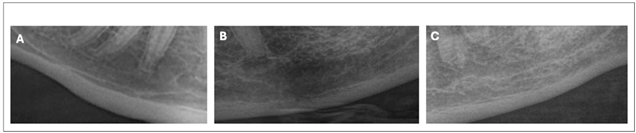

自动裁切为矩形并聚焦于颏孔区域的影像:(A)年轻患者,(B)无骨质疏松的老年患者,(C)患有骨质疏松的老年患者。